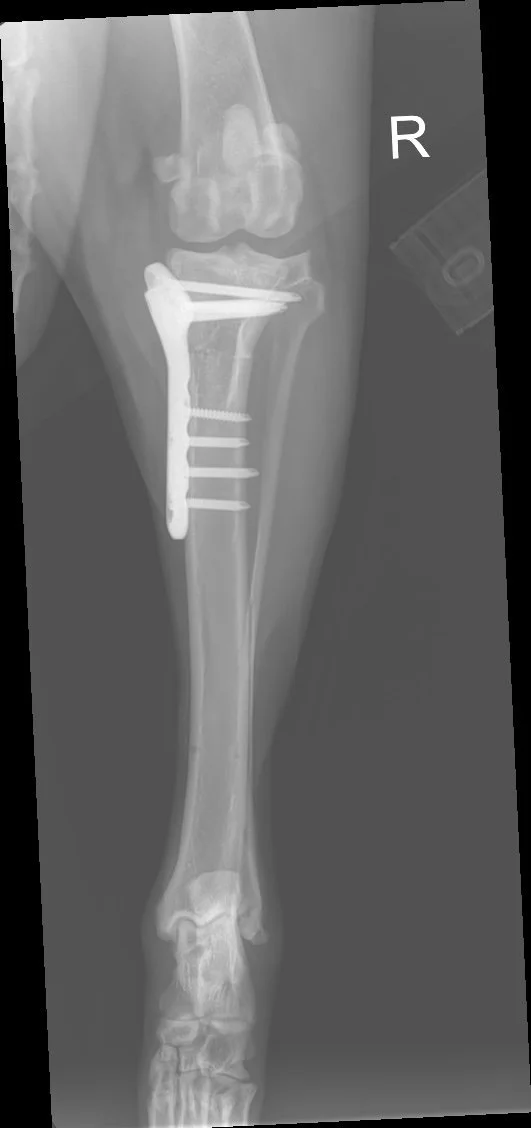

1. Preoperative Assessment: Detailed radiographs are taken to measure the existing angle of the tibial plateau and plan the surgical approach.

2. Surgical Technique: Under general anaesthesia, a curved cut (osteotomy) is made in the top portion of the tibia. This segment is then rotated to achieve a more level orientation, typically aiming for an angle between 5 to 6 degrees.

3. Stabilization: The repositioned bone is secured using a specially designed metal plate and screws, ensuring stability as the bone heals in its new alignment.

Recovery from TPLO surgery typically spans 8 to 12 weeks. During this period, controlled exercise and adherence to postoperative guidelines are essential. Follow-up radiographs are usually performed around 6 weeks post-surgery to assess bone healing. Most dogs regain full function and return to their normal lifestyle and exercise regime once their recovery is complete.